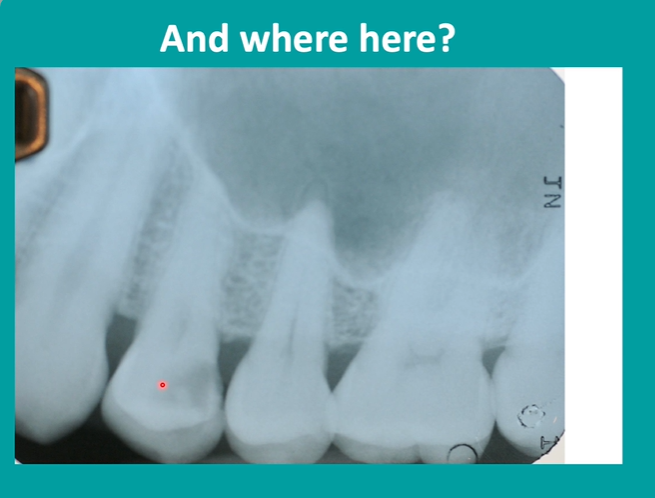

bitewing radiographs in caries detection

electrons need to hit the detector at 90 degrees so we get no crossover of the contact areas

distal of premolar

radiolucency